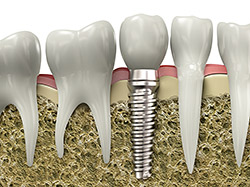

An implant is a synthetic tooth root in the shape of a post that is surgically placed into the jawbone. The “root” is usually made of titanium (the same material used in many replacement hips and knees), a metal that is well suited to pairing with human bone. A replacement tooth is then fixed to the post. The tooth can be either permanently attached or removable. Permanent teeth are more stable and feel more like natural teeth.

implantsImplants are versatile. If you are only missing one tooth, one implant plus one replacement tooth will do the trick. If you are missing several teeth in a row, a few strategically placed implants can support a permanent bridge (a set of replacement teeth). Similarly, if you have lost all of your teeth, a full bridge or full denture can be permanently fixed in your mouth with a strategic number of implants.